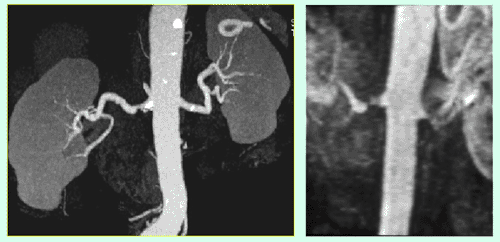

Abbildung 1a,b: CTA und MRA bei Nierenarterien-Stenose

Abbildung 3a,b: Junge Frau mit Bluthochdruck – Nierenarterien-Stenose rechts (FMD) vor und nach PTA

Abbildung 4a,b: Älterer Herr mit eingeschränkter Nierenfunktion, Bluthochdruck und Aortenaneurysma. CTA und Angiographie mit Nierenarterien-Stenose links.

Abbildung 5a,b: Derselbe Patient wie Abb. 4. Das Aneurysma wurde mit einem Stentgraft behandelt. MRA Kontrolle des Stentgrafts mit Darstellung der Nierenarterien-Stenose links.